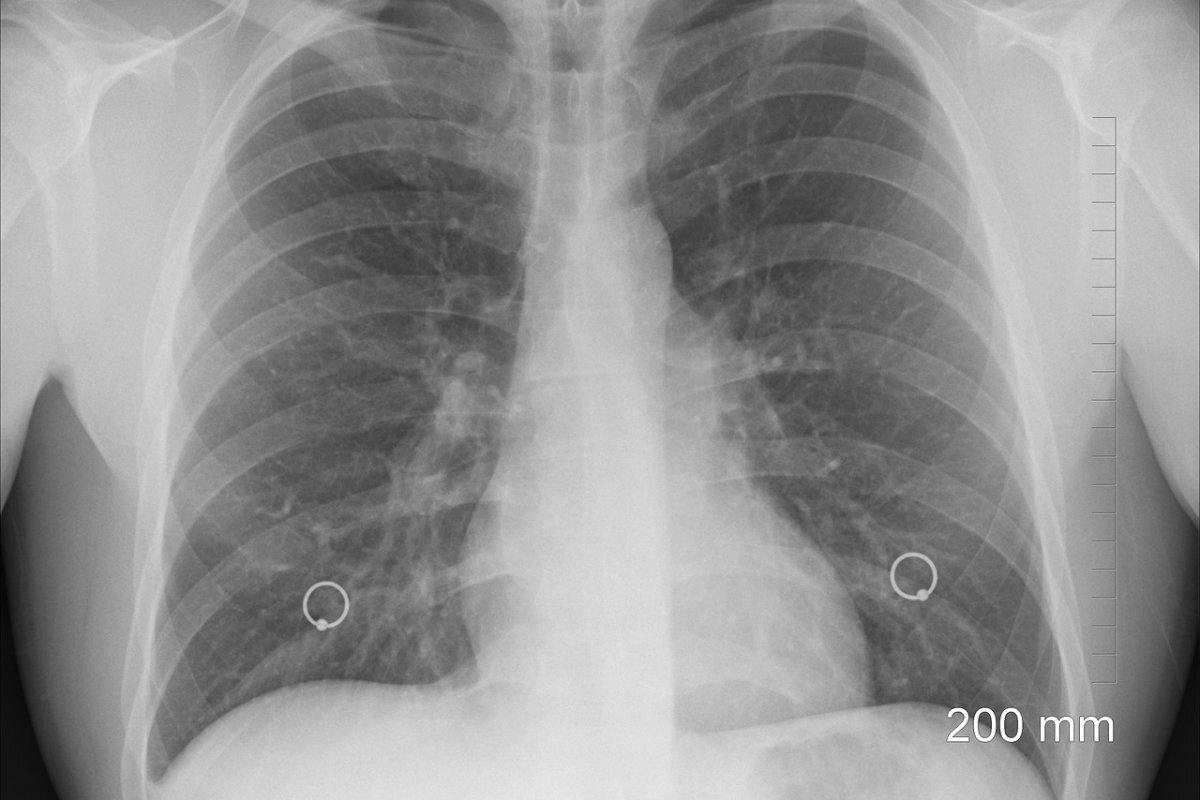

Боль в груди при кашле может быть симптомом плеврита